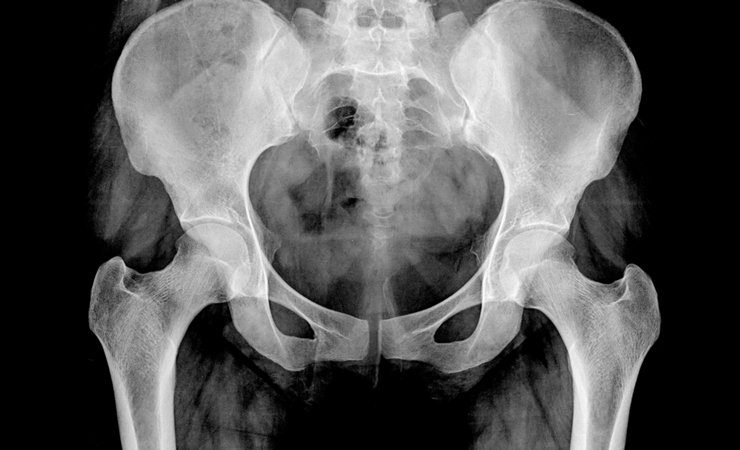

骨盤がゆがむと命にかかわる病気も……CT検査で関節チェック!

臓器に対しては磁気共鳴を利用したMRI検査や、超音波を利用した超音波(エコー)検査などがありますが、骨格そのものをチェックするには「CT検査」という連続エックス線撮影による断層画像検査がおすすめです。

連続的にエックス線で断層画像を撮影し、それをつなげて解析することで、パーツパーツの骨格の状態やつながりの状態、位置関係を視診できるのがCT検査です。